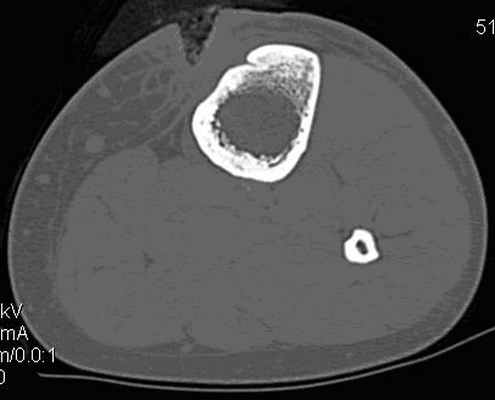

Компьютерная томография имеет более высокую инфрмативность и в определении стадии остеомиелита, так как дает возможность получения изображения на интересуемом уровне в аксиальной проекции и проведения не только качественной, но и количественной оценки. С помощью компьютерной томографии у половины пациентов (20 человек - 50%) удалось выявить особенности костной деструкции, визуализировать секвестры, воспалительные кисты в мягких тканях, параоссальные флегмоны, абсцессы и другие изменения, которые не определялись рентгенологически. Кроме того, проведенные томографические исследования позволяли четко определиться с анатомическим расположением патологического очага, его взаимосвязью с окружающими структурами (рис. 4, 5). Компьютерная томография повлияла на принятие тактического решения у 11 пациентов (27,5%). С помощью КТ-фистулографии у 19 (47,5%) пациентов дополнительно определялось распространение контрастного препарата по свищевым ходам как в мягких тканях, так и в кости. Во всех случаях выявленные поражения на КТ-фистулографии подтвердились операционными данными.

Рис. 5. Компьютерная томограмма левой голени пациентки Н., 18 лет с хроническим посттравматическим остеомиелитом. Определяется деструкция передней части компактной пластины большеберцовой кости

(Справа) КТ без контрастирования, аксиальный срез: определяется классический хронический остеомиелит. Отмечается обширное периостальное формирование зрелой новой кости вокруг диафиза большеберцовой костив и, в меньшей степени, вдоль малоберцовой кости. Кортикальный эндост также заметно утолщен. Такая выраженная реакция характерна для хронической инфекции.